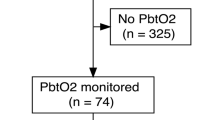

Prospectively recorded observational data of 51 consecutive spontaneous ICH patients fulfilling the inclusion/exclusion criteria for multimodal neuromonitoring admitted to the neurological intensive care unit (NICU) at a tertiary care center between 2011–2018 were studied. Neuromonitoring was initiated after hematoma evacuation (HE) in all patients and comprised assessment of brain tissue oxygen tension (PbtO2), intracranial pressure (ICP), and cerebral perfusion pressure (CPP). Patients were excluded if PbtO2 probes were dysfunctional (n = 7) or when recording time was less than 12 h (n = 4), leaving 40 patients eligible for the final analysis (Fig. 1). General inclusion criteria encompassed (1) admission with non-traumatic ICH diagnosed on cerebral imaging, (2) age ≥ 18 years, (3) hematoma evacuation, including the placement of invasive multimodal neuromonitoring as part of routine clinical care. The study was approved by the local ethics committee of the Medical University of Innsbruck (AN4088292/4.3, AM4091-292/4.6). Informed consent was obtained from all patients according to local regulations in accordance with the ethical standards as laid down in the 1964 Declaration of Helsinki. The reporting of data conforms to the STROBE guidelines.